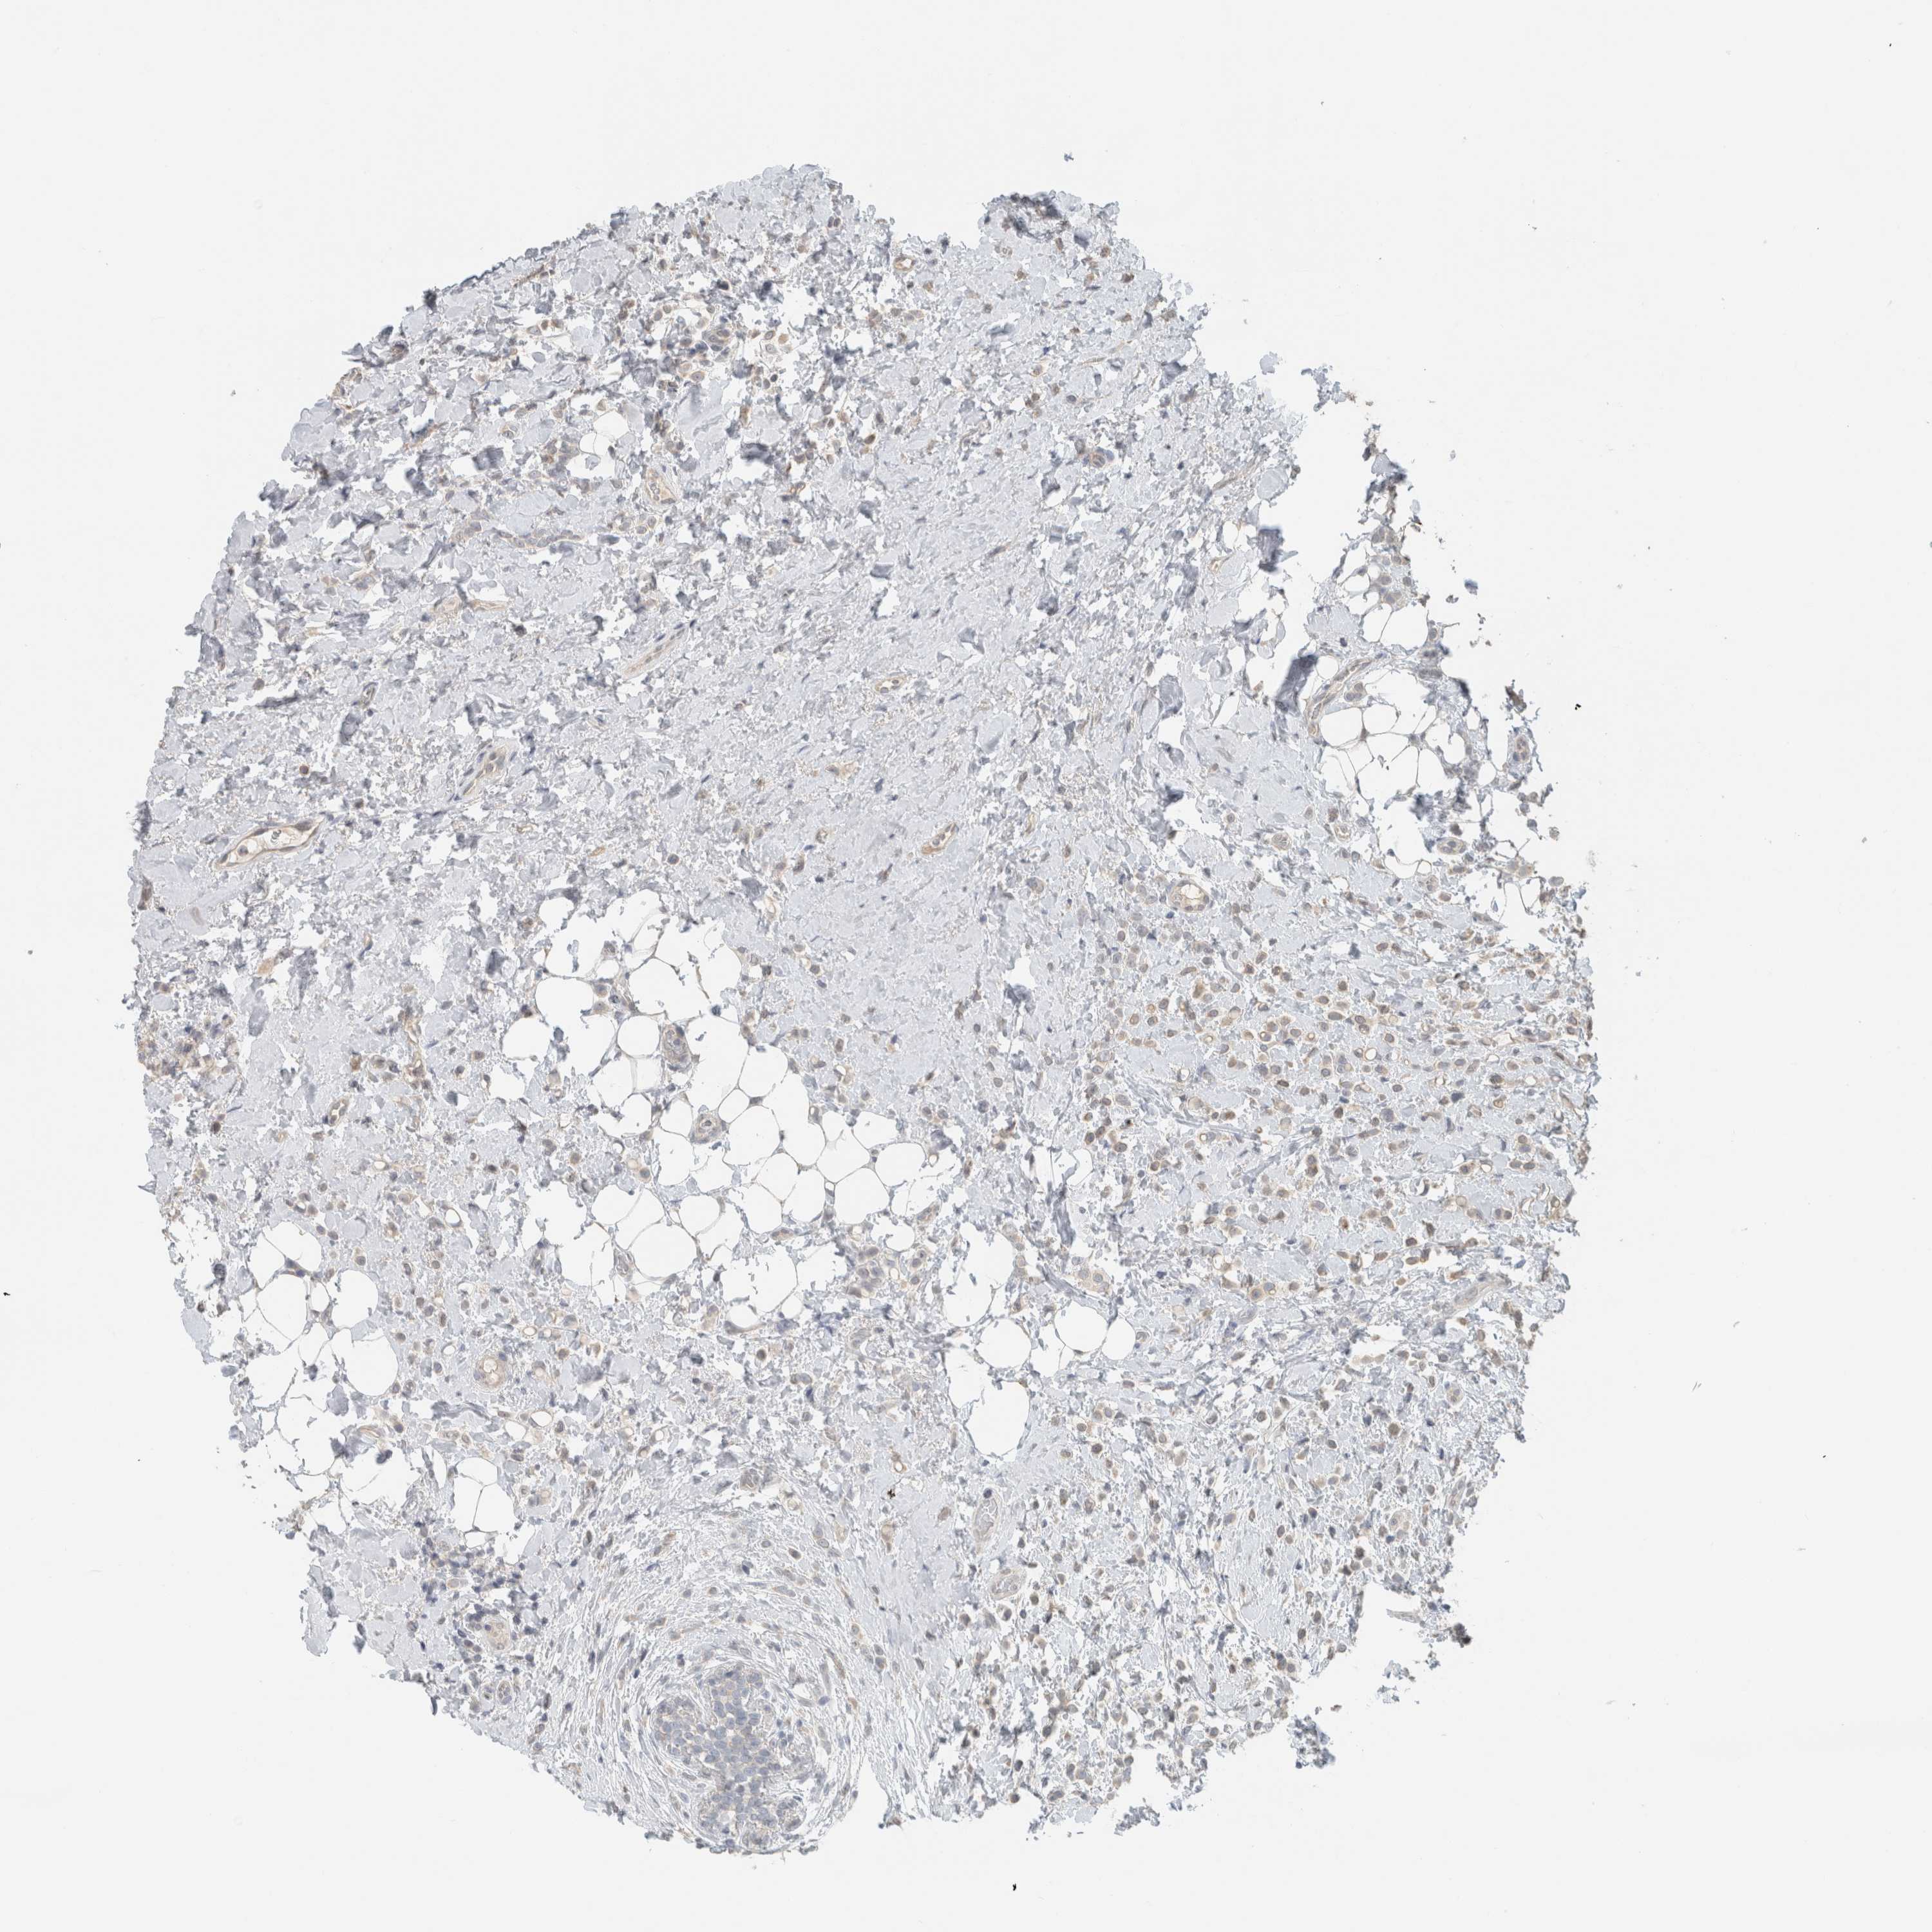

BRCA TCGA BRCA VALIDATION PROTEIN EXPRESSION

ANTIBODIES

AND

VALIDATION